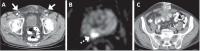

Objective: To investigate clinical, pathology, and imaging findings associated with inguinal lymph node (LN) metastases in patients with prostate cancer (PCa).

Materials and methods: This was a retrospective single-center study of patients with PCa who underwent imaging and inguinal LN biopsy between 2000 and 2023. We assessed the following aspects on multimodality imaging: inguinal LN morphology; extrainguinal lymphadenopathy; the extent of primary and recurrent tumors; and non-nodal metastases. Imaging, clinical, and pathology features were compared between patients with and without metastatic inguinal LNs.

Results: We evaluated 79 patients, of whom 38 (48.1%) had pathology-proven inguinal LN metastasis. Certain imaging aspects- short-axis diameter, prostate-specific membrane antigen uptake on positron-emission tomography, membranous urethra involvement by the tumor, extra-inguinal lymphadenopathy, and distant metastases-were associated with pathology-proven inguinal LN metastases (p < 0.01 for all). Associations with long-axis diameter, fatty hilum, laterality, and uptake of other tracers on positronemission tomography were not significant (p = 0.09-1.00). The patients with metastatic inguinal LNs had higher prostate-specific antigen levels and more commonly had castration-resistant PCa (p < 0.01), whereas age, histological grade, and treatment type were not significant factors (p = 0.07-0.37). None of the patients had inguinal LN metastasis in the absence of locally advanced disease with membranous urethra involvement or distant metastasis.

Conclusion: Several imaging, clinical, and pathology features are associated with inguinal LN metastases in patients with PCa. Isolated metastasis to inguinal LNs is extremely rare and unlikely to occur in the absence of high-risk imaging, clinical, or pathology features.